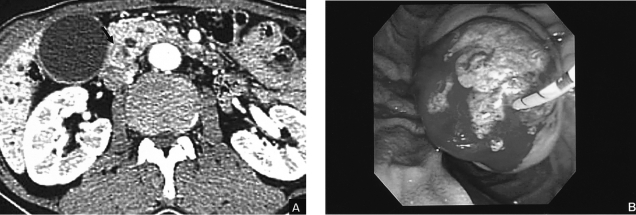

A 71-year-old Korean man was admitted to our hospital with epigastric pain and general weakness. The ocular conjunctiva was icteric. His abdomen was soft and no mass was palpable. The blood chemistry revealed Hgb 12.5 g/dL, bilirubin 1.3 mg/dL, ALP 1879 U/L and GGT 89 U/L. Tumor markers were CA19-9 8.5 U/mL, CEA 8.5 ng/mL and CA-125 7.46 U/mL which were within normal limits. The patient's abdominal computed tomography (CT) showed a mass, with contrast enhancement, at the ampulla of Vater and dilatation of the bile duct as well as the main pancreatic duct (Figure 1A). His duodenoscopy showed a reddish protruding tumor mass at the ampulla of Vater (Figure 1B). The endoscopic ultrasonography demonstrated a hypoechoic mass at the ampulla of Vater without any invasion into the duodenal muscularis propria layer, or pancreatic parenchyma; the mass measured 25×25 mm in size. The endoscopic biopsy of the tumor showed a well-differentiated adenocarcinoma (Figure 3A). The patient underwent pylorus preserving pancreatico-duodenectomy; the resection margins were intact histologically. The tumor size was 25×25×10 mm in diameter. The results of the microscopic examination along with dissection of six lymph nodes confirmed that the lymph nodes did not have any tumor cells. Invasion of the lymphatic and venous systems were not found histologically; however, focal invasion of the common bile duct was observed. Therefore, the tumor was stage I (T2N0M0). The patient recovered without any complication.

Figure 1

(A) Abdominal computed tomography shows a mass 2.5 cm in diameter at the ampulla of Vater. (B) Endoscopic findings show a protruded mass into the ampulla of Vater.